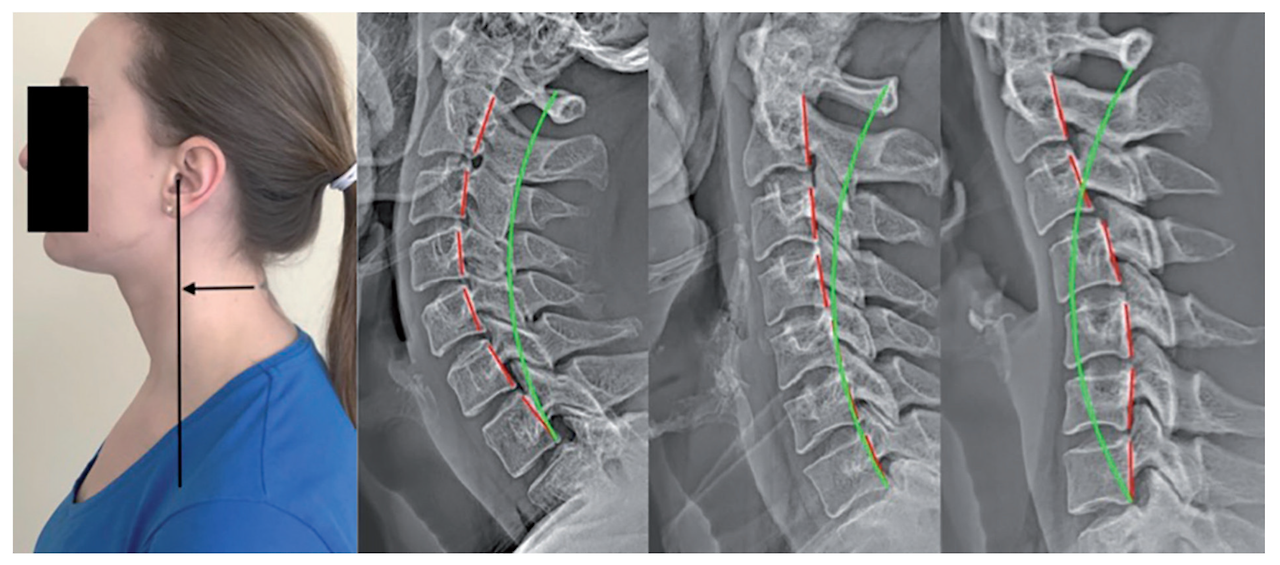

이 신호의 핵심 원인은 바로 **전방머리자세(Forward Head Posture, FHP)**입니다.

머리가 어깨보다 앞으로 빠져 있는 이 자세는 흔히 ‘일자목’, ‘거북목’이라고 불리며, 현대인에게 너무나 익숙한 모습이 되었습니다. 문제는 이 자세가 단순히 목만 불편하게 만드는 것이 아니라, 뇌로 가는 혈류를 방해하고 신경을 압박하여 두통·현훈·구토까지 이어질 수 있다는 점입니다.

좁은 좌석, 전방 주시 자세, 차량 진동은 모두 **두개-척추각(CVA, Craniovertebral Angle)**을 줄여 거북목을 심화시키는 요인입니다.

한 신경외과 교수는 “CVA가 작을수록 현훈 지수(DHI)가 높아지고, 경추 고유수용성 오류(JPE)가 증가한다”며, 목이 앞으로 나가면 단순 통증이 아니라 균형감각과 신경계 정확성까지 무너진다고 설명합니다.